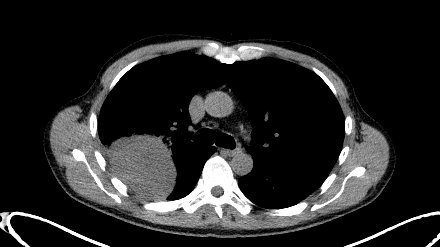

Massa baseada na pleura direita, com necrose parcial, associada a múltiplos pequenos nódulos satélites também pleurais (não evidenciados nesta imagem).